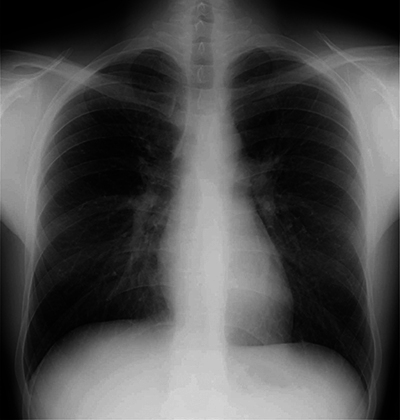

A case of complete recovery of negative pressure pulmonary edema after a Cottle surgery in a 24-year-old male. Teaching point: Negative pressure pulmonary edema is an important cause of postoperative noncardiogenic edema, with the spontaneous disappearance of all complaints within a relatively short period.

Abstract Image